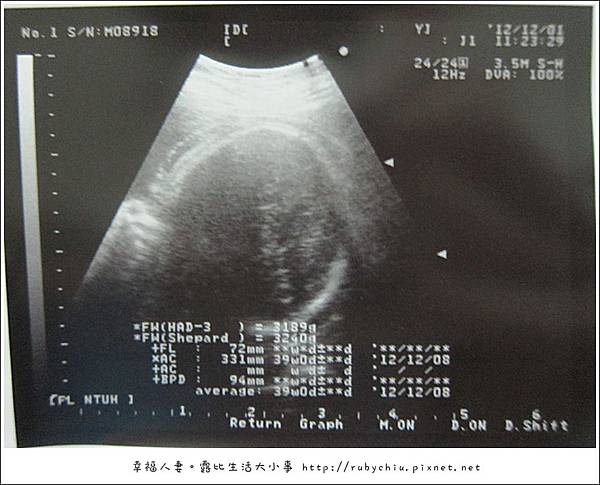

這次產檢啊!醫生說頭完全下來啦!差不多可以生了啦

本週紀念品體重3200g!頭圍94mm... 還有一週 不曉得她打算選12幾號出來哩!